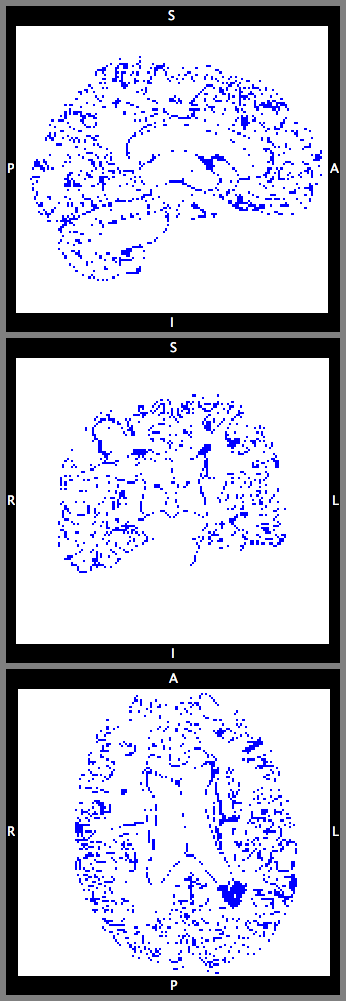

This section investigates the number of Monte Carlo samples and the segmentation performance of the proposed network. Fig. 8(a) suggests that using samples is enough to achieve good segmentation. Further increasing the number of samples has relatively small effects on the DCS. Fig. 8(b) plots the voxel-wise segmentation accuracy computed using only the voxels with an uncertainty less than a threshold. The voxel-wise accuracy is high when the threshold is small. This indicates that the uncertainty estimation reflects the confidence of the network. Fig. 9 shows an uncertainty map generated by the proposed network. The uncertainties near the boundaries of different structures are relatively higher than the other regions.

With this theoretical insight, we are able to estimate the uncertainty of the segmentation map at the voxel level. We extend the segmentation network with a convolutional layer before the last convolutional layer. The extended network is trained with a dropout ratio of 0.5 applied to the newly inserted layer. At test time, we sample the network N times using dropout. The final segmentation is obtained by majority voting. The percentage of samples which disagrees with the voting results is calculated at each voxel as the uncertainty estimates.